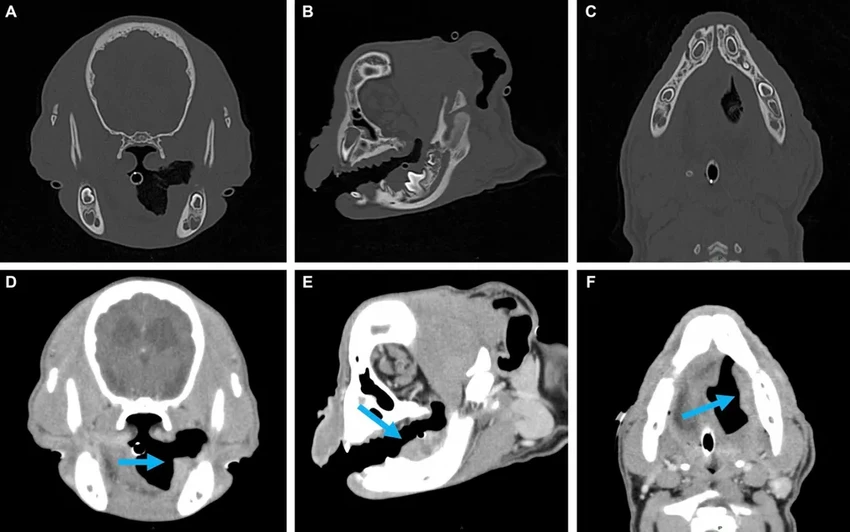

В отчете журнала Frontiers in Veterinary Science история расписана по дням. Весной 2023 года щенка привезли в клинику со злокачественной опухолью на левой стороне челюсти. Диагноз — плоскоклеточный рак, второй по распространенности тип рака ротовой полости у собак. Неужели приговор?

Операция прошла успешно. А потом случилось чудо, которое никто не ожидал. Всего через восемь недель ветеринары, осматривая Тайсона, остолбенели: на месте удаленной кости формировалась новая челюсть.

Почему так произошло? Учёные связывают это с двумя факторами: юным возрастом Тайсона и мастерством хирургов, которые во время операции максимально сохранили надкостницу — ту самую живую оболочку кости, пронизанную сосудами. Именно она, вероятно, и стала «чертежом» для новой челюсти. Но вот как именно сработал этот механизм — загадка. Можно ли повторить это у других собак? Пока ответа нет.

Новая челюсть, конечно, не идеальная копия старой. Зубов на ней пока нет, и твердую пищу Тайсону есть нельзя. Но она полностью функциональна, симметрична и, что главное, — чиста от рака. Разве это не потрясающе?